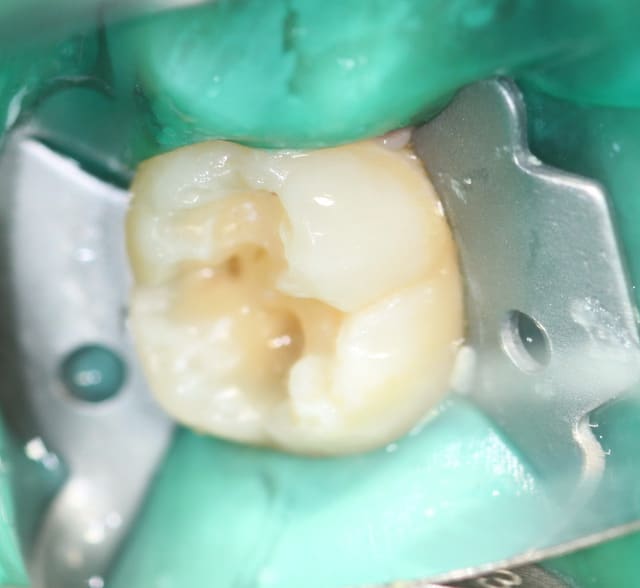

voila finalement on a opter pour la conservation de la dent...

Décapuchonné à la lame froide saignement modéré (infiltration d’anesthésie adrénalinée tout autours de la couronne... Un point de suture dix jours après compo. conseils d’hygiène.

très très beau boulot Charlotte!

chapeau pour la digue là bas!